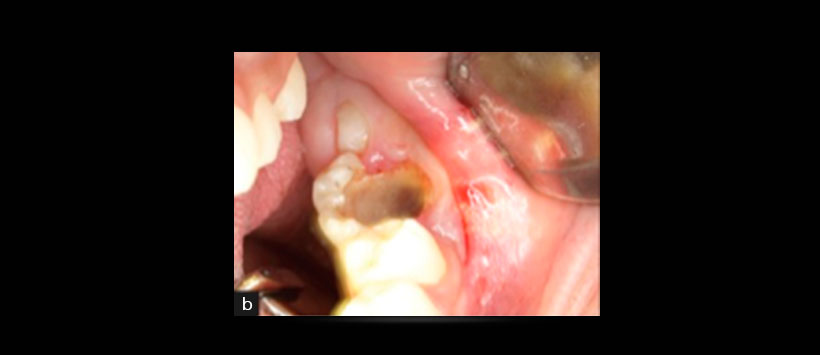

Figura 2: Fotografía intraoral que muestra el aumento de volúmen de la tabla ósea vestibular a nivel de la pieza 3.6 y que ocasiona el borramiento del fondo de surco.